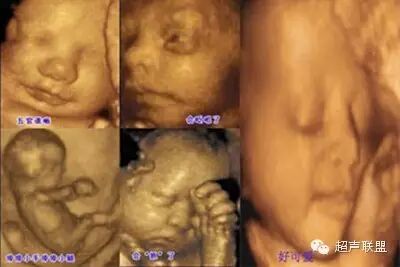

近年来,颜面部结构的辨认与颜面部畸形的产前超声诊断越来越受到人们的重视,三维超声的飞速发展,能将颜面部结构及畸形非常逼真地展现在人们面前。随着超声仪器的不断发展,图像分辨力的不断提高,颜面部的许多细小结构及某些面部表情亦能清晰可辨,如胎儿人中的显示,胎儿争眼、皱额等细微表情动作的显示与观察等。眼眶、眼球、眼裂、眼睑、前额、鼻、鼻骨、上下唇、人中、上颌骨及上牙槽突与其内的牙胚、下颌骨及下牙槽突与其内的牙胚、下颌、硬腭、舌、口、颧骨、耳廊等结构均能清晰可辨,因此,对这些正常结构的正确认识,对提高颜面部结构畸形的认识是非常有帮助的。

一、 胎儿正常颜面部的超声解剖